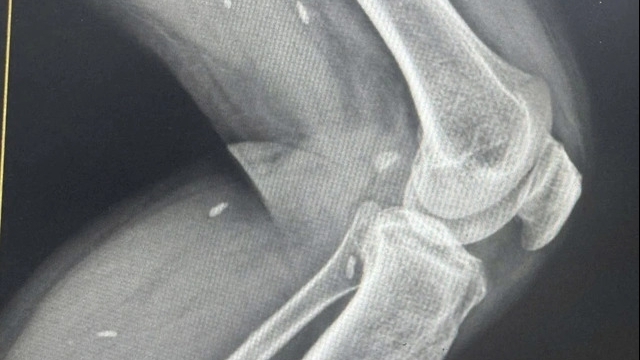

| Bệnh nhân trong tình trạng xuất huyết hoại tử toàn thân (Ảnh: BVCC) |

Các bác sĩ chẩn đoán bệnh nhân bị sốc nhiễm khuẩn, suy đa tạng, theo dõi liên cầu lợn. Bệnh nhân có co giật, được đặt ống nội khí quản, thở máy, duy trì vận mạch...

Tại đây, các bác sĩ kết luận bệnh nhân bị sốc nhiễm khuẩn, nhiễm khuẩn huyết và viêm màng não do liên cầu lợn. Hiện tại, bệnh nhân vẫn đang trong tình trạng nguy kịch, suy đa tạng, thở máy.